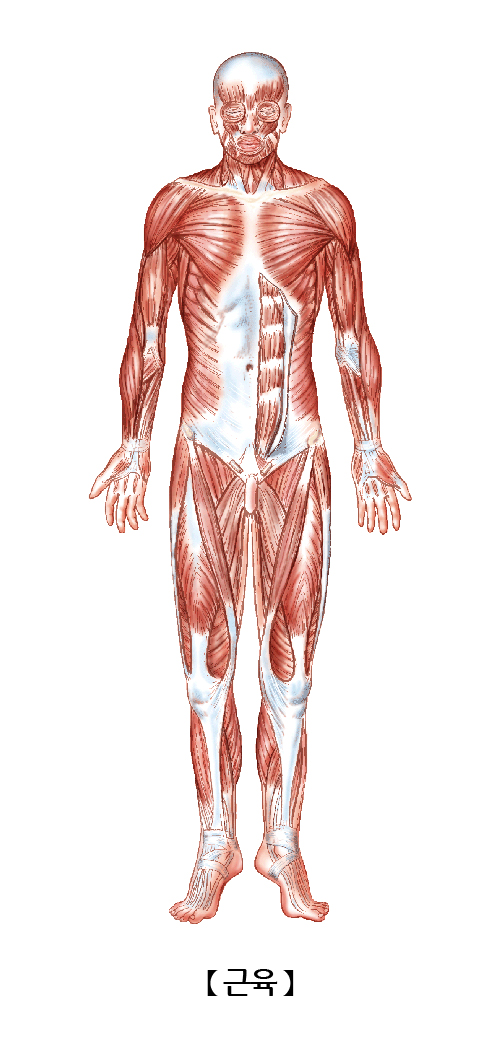

근육(Muscle)

우리 몸의 골격을 이루는 뼈에 부착하여 운동을 가능하게 해주는 기관입니다. 우리 몸의 근육은 크게 골격근, 심장근, 내장근으로 구분할 수 있으며 기능에 따라 자신의 의사로 수축을 조절할 수 있는 수의근과 수축을 조절할 수 없는 불수의근, 모양에 따라 가로무늬근과 민무늬근으로 나눌 수 있습니다.

우리 몸의 운동을 담당하는 모든 부위에 위치합니다.

근육은 우리 몸의 움직임과 조작을 담당하며 자세를 유지시켜주고 관절을 연장시켜줍니다. 뿐만 아니라 심장과 내장기관을 움직여 생명유지하는데 중요한 기능을 합니다.